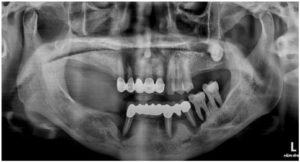

정밀한 검사를 위해

파노라마 사진을 촬영해 보았더니

아래턱 치아들이

심각한 골흡수를 보이고 있는

만성 치주염 상태로

전체 발치가 불가피한 상황이었습니다.